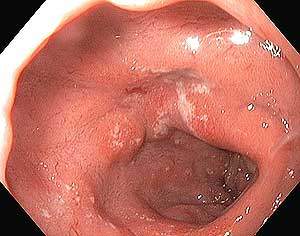

Mide (gastroskopi) aşaması

LES geçildikten sonra mideye girilir. Midenin fundus, kardia, korpus, antrum ve pylor bölgeleri incelenir. Mide içerisinde görülecek önemli hastalıklar şöyledir: mide iç duvarının belirli bir bölgesinin (Antral Gastrit) veya tamamının (pangastrit) iltihaplanması, derin veya yüzeysel yaraların oluşması (peptik ülser), safraya bağlı iltihap oluşması (alkalen reflü gastrit), polipler, ve iyi huylu (benign) veya kötü (malignant) tümörler ve mide çıkışının daralması (pylor stenozu veya Gastric outlet obstruction).